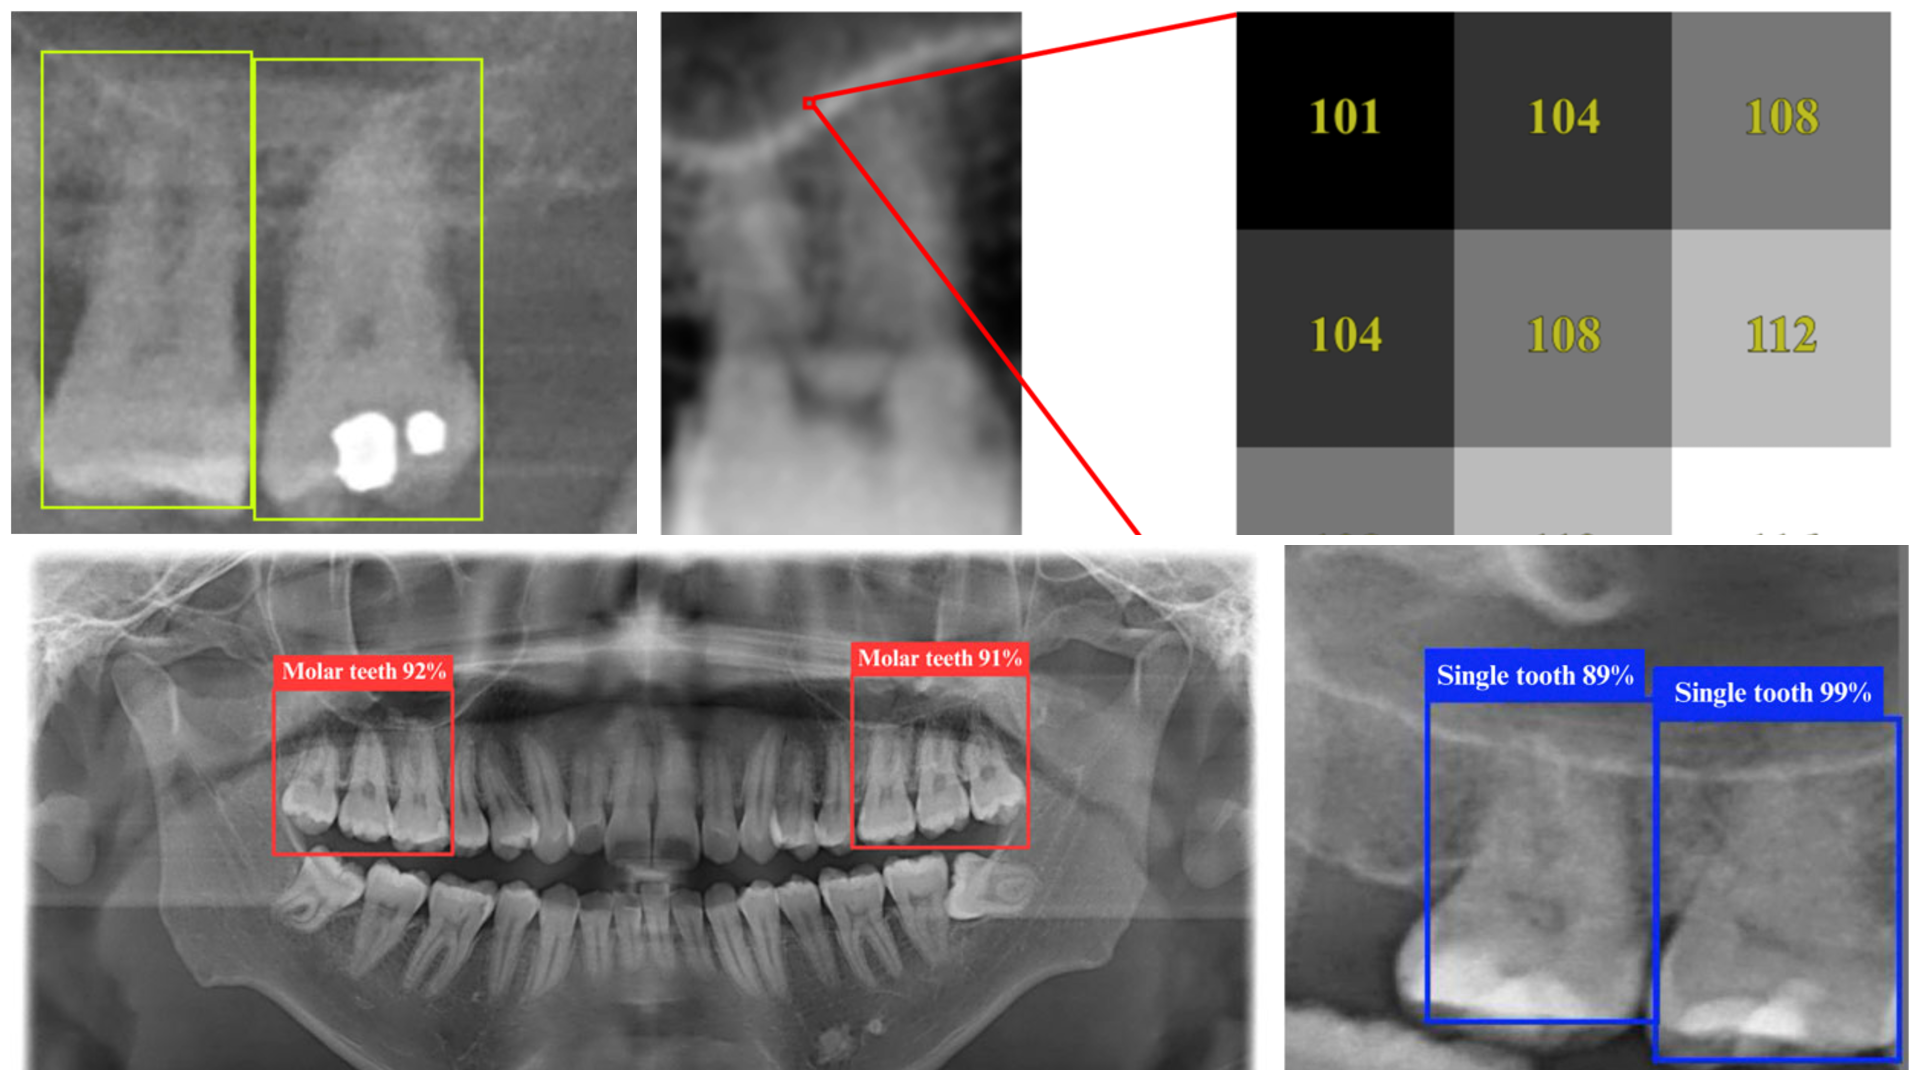

DPR dental x-ray images sampled using the YOLO algorithm

Sample dental X-rays or dental panoramic radiographs (DPRs) as seen by the YOLO 11n deep learning model. CREDIT: Pei-Yi Wu et al., 2025

By training deep learning models on dental panoramic radiograph (DPR) images, the researchers found a way to detect key anatomical relationships—such as the proximity of tooth roots to sinuses—with unprecedented accuracy. The study used the YOLO 11n deep learning model, achieving an impressive 98.2% accuracy, outperforming traditional detection methods.

YOLO (You Only Look Once) is a state-of-the-art object detection algorithm known for its speed and accuracy. The YOLO 11n model, an improved version, is optimized for medical imaging tasks, enabling it to identify teeth and sinus structures with high precision in a single pass through the image. Unlike conventional diagnostic methods, which require multiple steps and expert interpretation, YOLO 11n rapidly pinpoints the affected areas in real time, making it an invaluable tool for dental professionals.